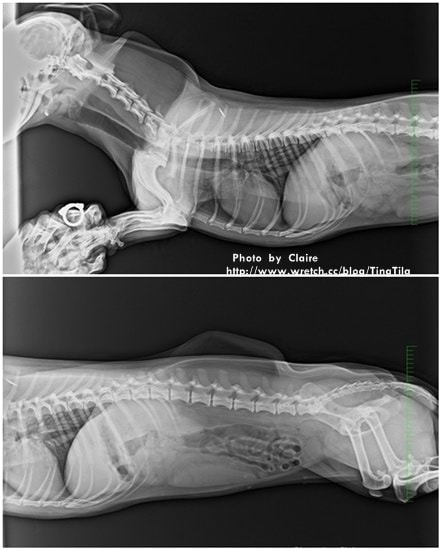

這是在拍X光

X光拍2組

一組TILA有兩張照片,一共四張

(看得到我自己的手耶…戒指也拍出來)

頭頸椎的狀況都很良好

CHD目前為二級

右側關節約為92度

左側關節約為79度

骨頭越掉出來,角度會越小

目前看起來~左腳會覺得比較差一點

而TILA的右腳如果感覺到不舒服沒有力氣的時候

就會把重心移給左腳,故左腳承受的壓力會比較大

但CHD這方面還不需要太擔心

重點還是要放在第七腰椎和XXXX(講太快,我既不清楚)之間的壓迫

也就是馬尾束症候群

TILA靠近尾巴那附近的脊椎神經叢有受到壓迫…

脊椎到後腰椎部的範圍~有眾多的神經根,因為神經根湊在一起形成神經叢

看起來就跟馬尾很像,當骨頭壓迫到神經叢的時候就會產生馬尾束症候群